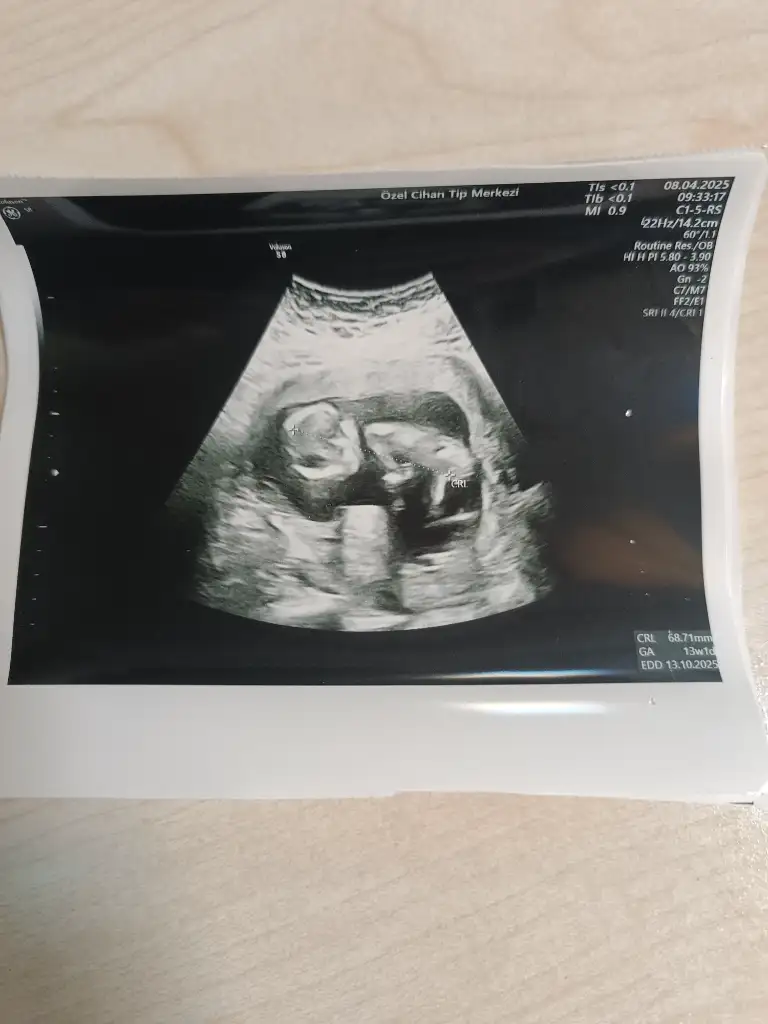

Benim bebişe de bakar mısın rica etsem, 13+1 haftalıkNuba bakarsak kız gibi duruyor![]()